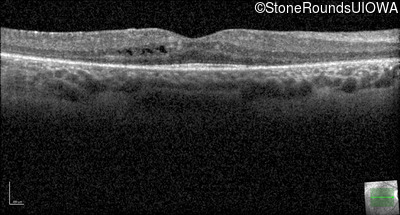

Optical Coherence Tomography - Right - 20/25 -2

Exemplar / OCT Stack